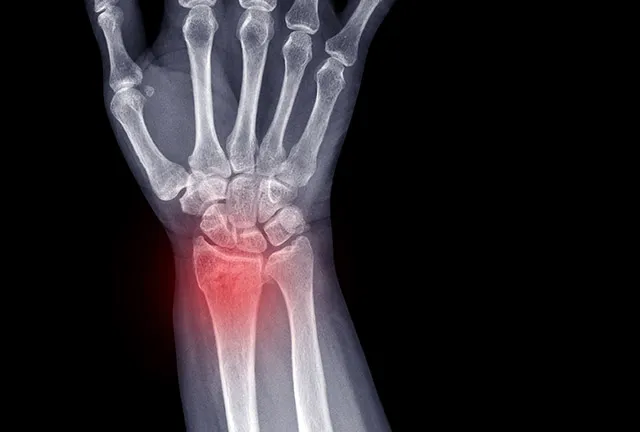

Rodzaj złamania

To absolutnie fundamentalna kwestia. Złamania bez przemieszczenia, czyli takie, gdzie kości pozostają w prawidłowym ułożeniu, goją się zazwyczaj szybciej i wymagają mniej inwazyjnej rehabilitacji. Natomiast złamania z przemieszczeniem, otwarte, wieloodłamowe czy śródstawowe (czyli te, które obejmują powierzchnię stawową) znacząco wydłużają czas rekonwalescencji. Często wymagają one leczenia operacyjnego, co samo w sobie wprowadza dodatkowe wyzwania i wydłuża okres powrotu do zdrowia, ponieważ dochodzi do uszkodzenia tkanek miękkich i konieczności gojenia się rany pooperacyjnej.